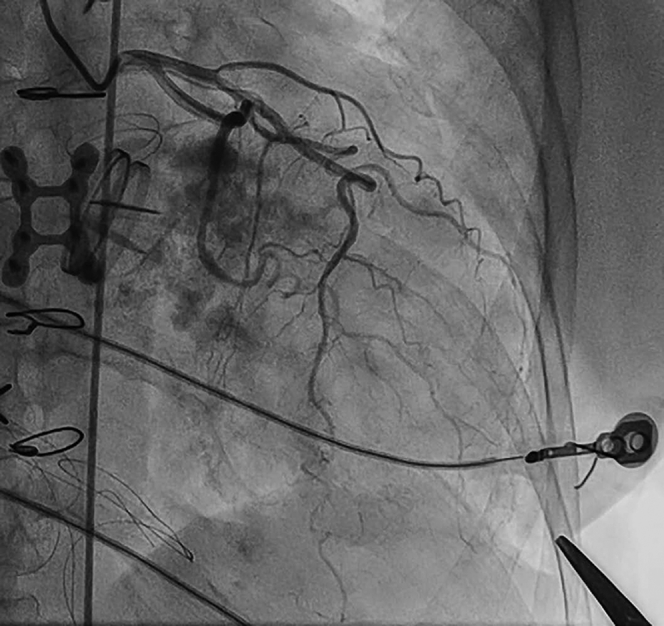

Fig 2.

Coronary angiography before transapical (TA) puncture. Once the apex is identified by palpation and transthoracic echocardiography (TEE), a marker (hemostat) is placed over the left ventricular apex and coronary angiography is performed. If the course of the left anterior descending artery is adequately distant from the marker, it is safe to proceed with percutaneous TA puncture.